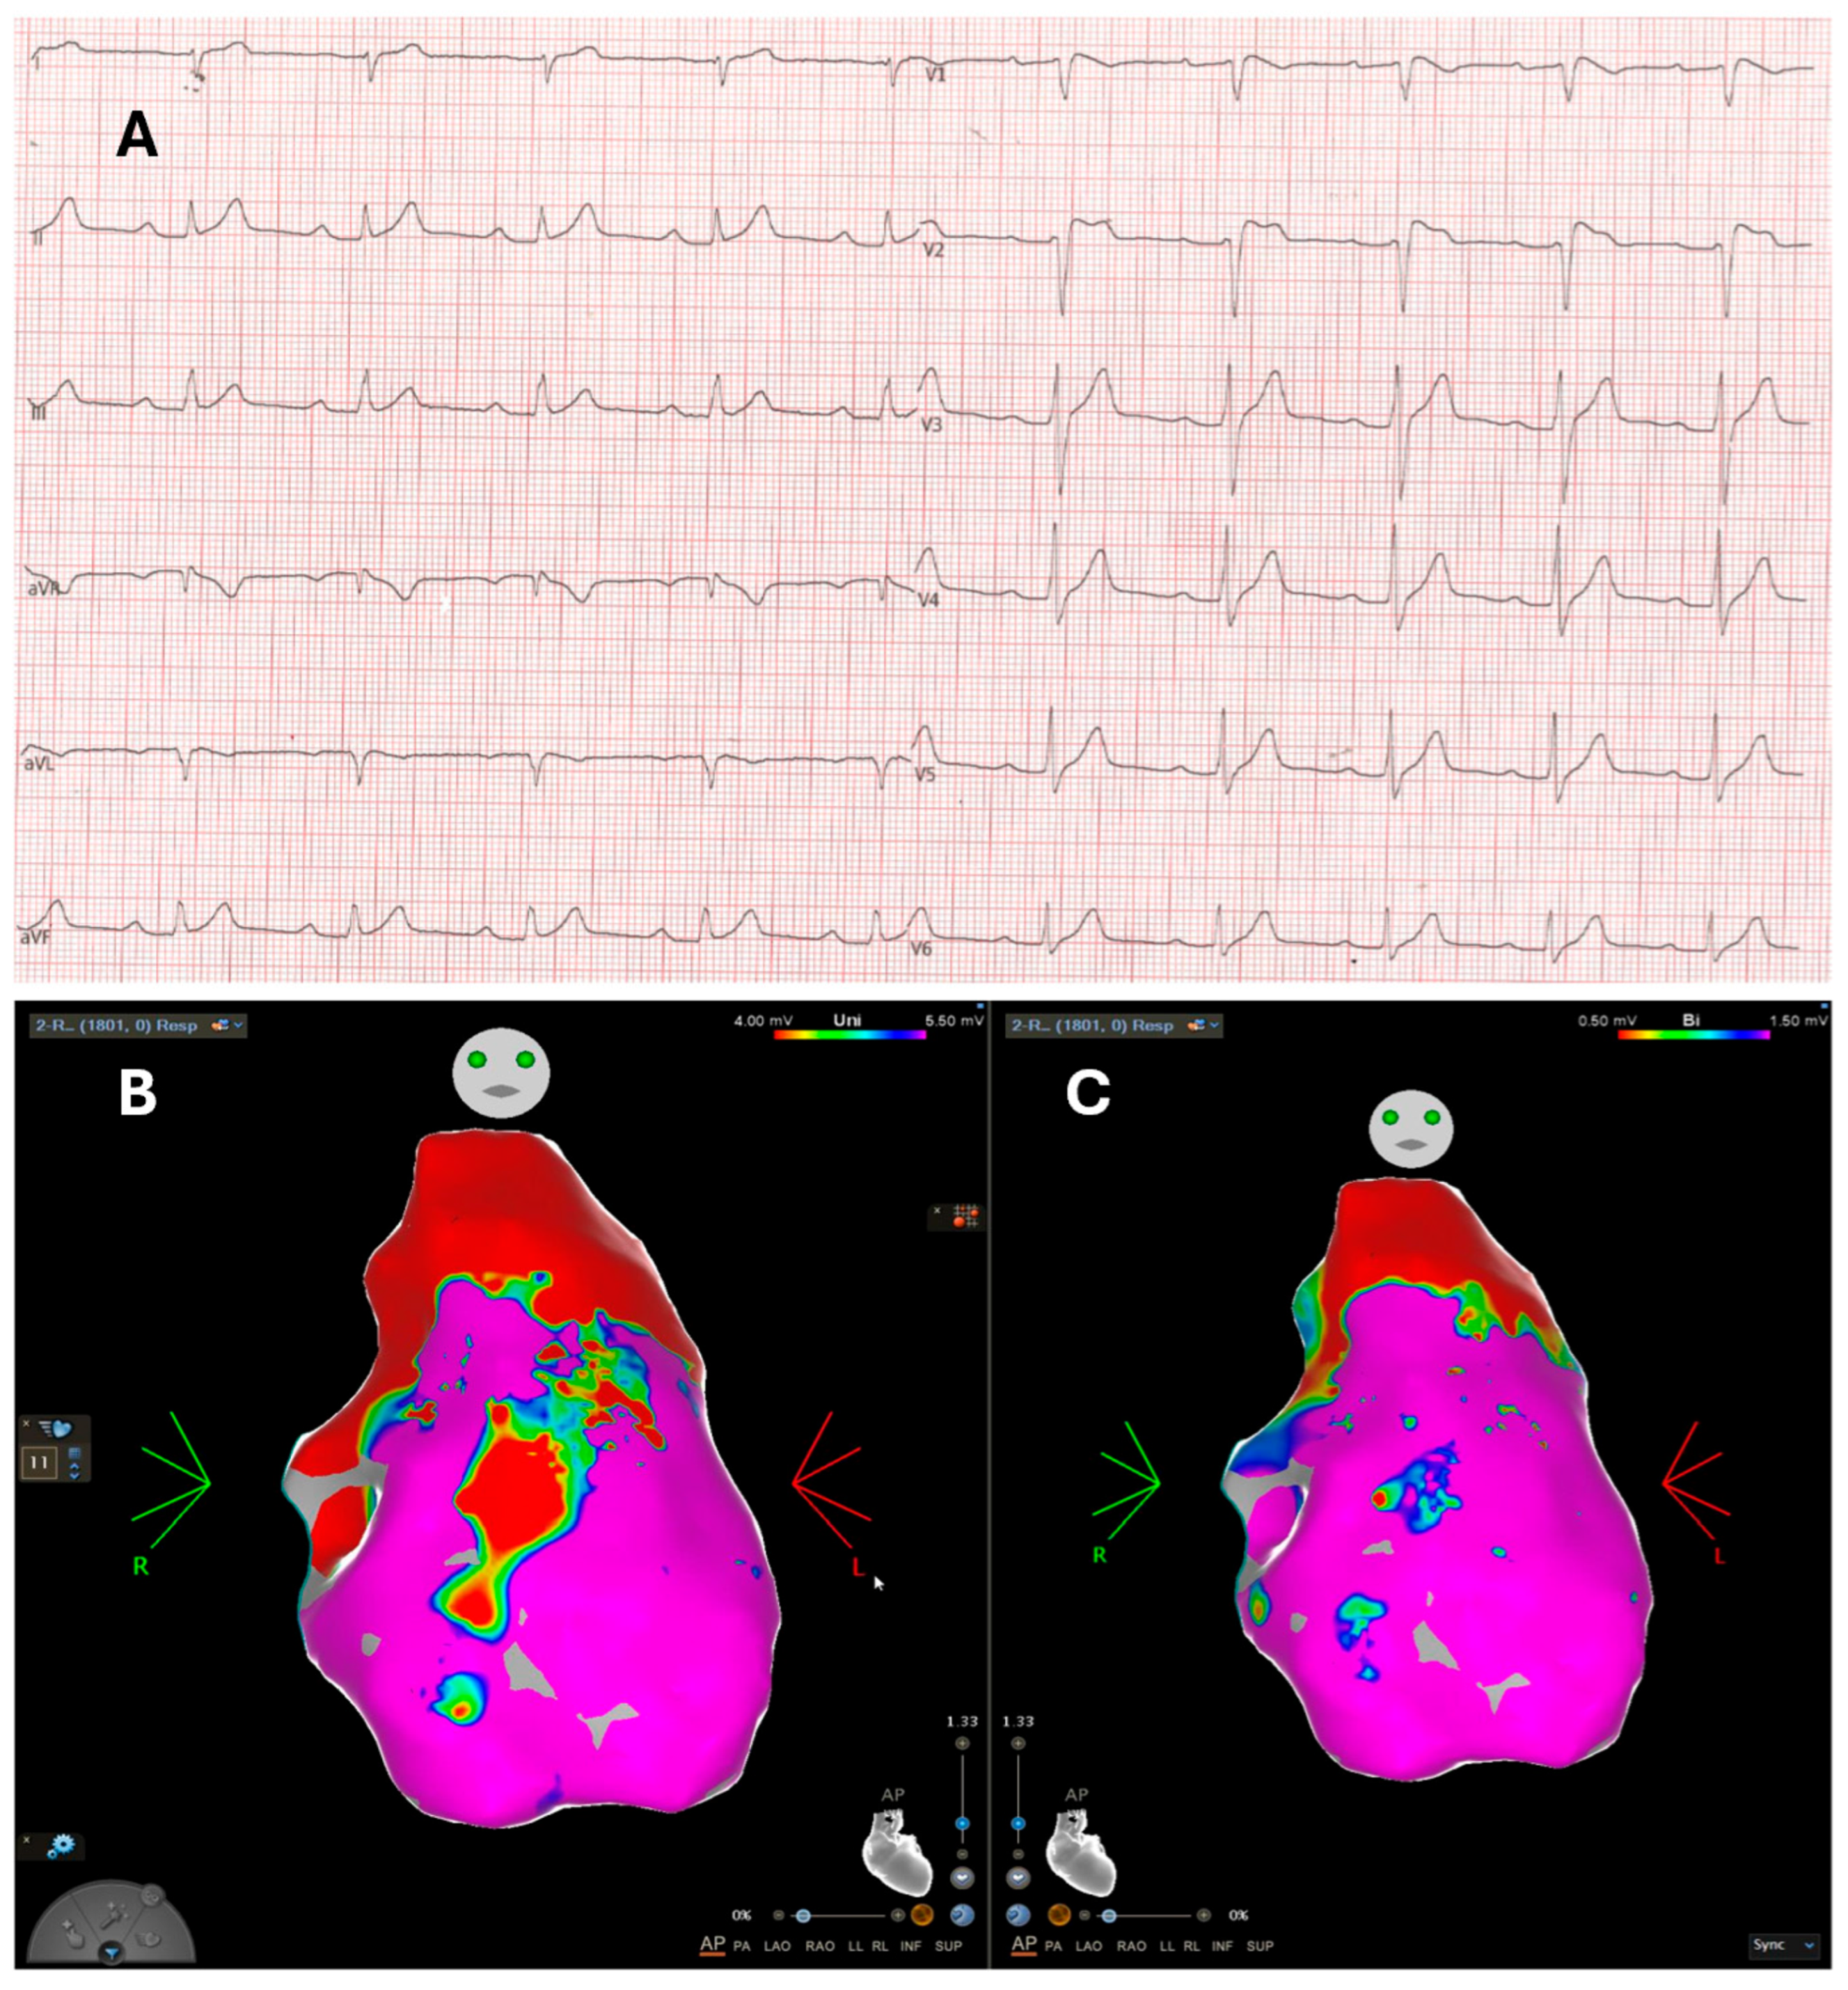

- Pieroni, M.; Notarstefano, P.; Oliva, A.; Campuzano, O.; Santangeli, P.; Coll, M.; Nesti, M.; Carnevali, A.; Fraticelli, A.; Iglesias, A.; et al. Electroanatomic and Pathologic Right Ventricular Outflow Tract Abnormalities in Patients With Brugada Syndrome. J. Am. Coll. Cardiol. 2018, 72, 2747–2757. [Google Scholar] [CrossRef]

- Pappone, C.; Ciconte, G.; Manguso, F.; Vicedomini, G.; Mecarocci, V.; Conti, M.; Giannelli, L.; Pozzi, P.; Borrelli, V.; Menicanti, L.; et al. Assessing the Malignant Ventricular Arrhythmic Substrate in Patients With Brugada Syndrome. J. Am. Coll. Cardiol. 2018, 71, 1631–1646. [Google Scholar] [CrossRef]

- Lambiase, P.D.; Ahmed, A.K.; Ciaccio, E.J.; Brugada, R.; Lizotte, E.; Chaubey, S.; Ben-Simon, R.; Chow, A.W.; Lowe, M.D.; McKenna, W.J. High-density substrate mapping in brugada syndrome: Combined role of conduction and repolarization heterogeneities in arrhythmogenesis. Circulation 2009, 120, 106–117. [Google Scholar] [CrossRef]

- Brugada, J.; Pappone, C.; Berruezo, A.; Vicedomini, G.; Manguso, F.; Ciconte, G.; Giannelli, L.; Santinelli, V. Brugada Syndrome Phenotype Elimination by Epicardial Substrate Ablation. Circ. Arrhythm. Electrophysiol. 2015, 8, 1373–1381. [Google Scholar] [CrossRef]

- Pappone, C.; Brugada, J.; Vicedomini, G.; Ciconte, G.; Manguso, F.; Saviano, M.; Vitale, R.; Cuko, A.; Giannelli, L.; Calovic, Z.; et al. Electrical Substrate Elimination in 135 Consecutive Patients with Brugada Syndrome. Circ. Arrhythm. Electrophysiol. 2017, 10, e005053. [Google Scholar] [CrossRef]

- Cheniti, G.; Haissaguerre, M.; Dina, C.; Kamakura, T.; Duchateau, J.; Sacher, F.; Racine, H.P.; Surget, E.; Simonet, F.; Gourraud, J.B.; et al. Left Ventricular Abnormal Substrate in Brugada Syndrome. JACC Clin. Electrophysiol. 2023, 9, 2041–2051. [Google Scholar] [CrossRef]